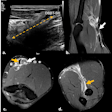

Left: Patient-connected imaging with ACROBEAT. The gantry trajectory and timing of the projection acquisition are adapted to the patient's ECG signal (red) as it evolves in real-time. Right: Conventional multisweep retrospectively ECG-gated acquisition. The gantry trajectory and timing of the projection acquisition are constant throughout the duration of the scan. Image courtesy of Reynolds et al, Phys Med Biol, 10.1088/1361-6560/ab03f4.

Left: Patient-connected imaging with ACROBEAT. The gantry trajectory and timing of the projection acquisition are adapted to the patient's ECG signal (red) as it evolves in real-time. Right: Conventional multisweep retrospectively ECG-gated acquisition. The gantry trajectory and timing of the projection acquisition are constant throughout the duration of the scan. Image courtesy of Reynolds et al, Phys Med Biol, 10.1088/1361-6560/ab03f4.The team examined acquisition windows of 30% to 40% and 60% to 70% through the cardiac cycle, representing optimal gating windows with minimal heart motion. They also investigated the 80% to 90% window, where large heart motion is observed, and a longer window spanning 60% to 80% of the cardiac cycle.